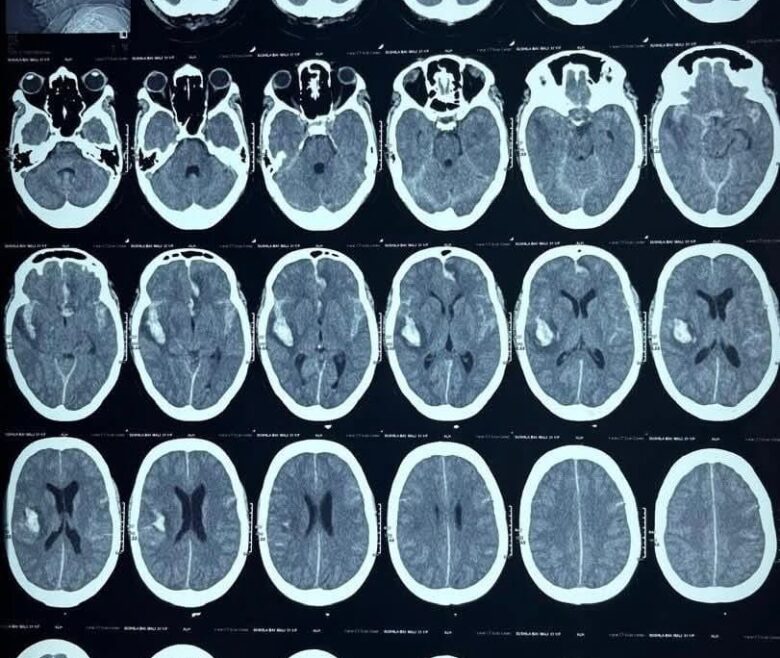

A Traumatic Brain Injury (TBI) is an injury to the brain caused by an external physical force, which results in temporary or permanent impairment of...